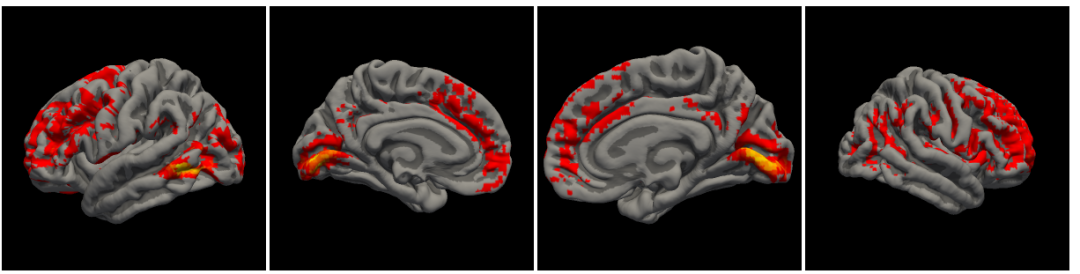

变换后的DK模板map到某个结果上